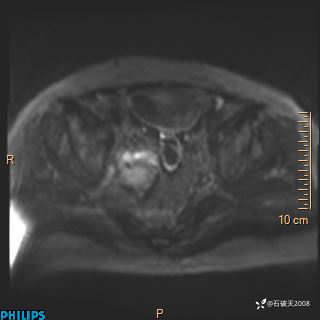

2023年3月份MRI影像

增强轴位